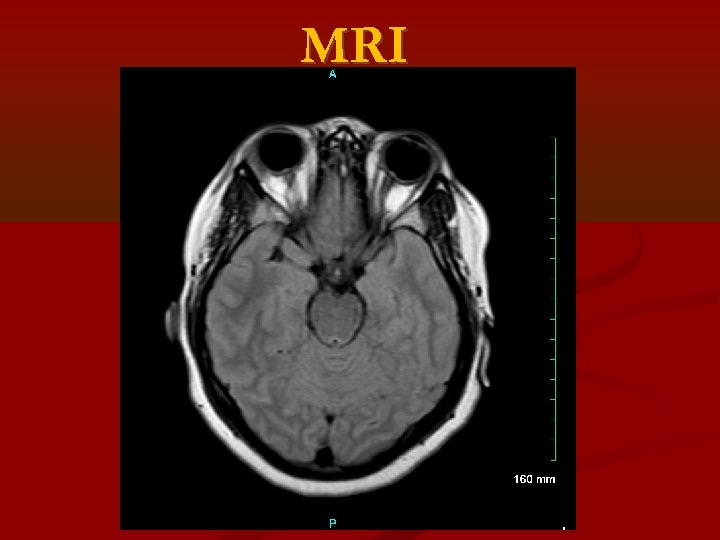

MRI

Idiopathic Intracranial Hypertension (IIH) MRI and MRV to rule out : • Cerebral venous disorders such as cerebral venous obstruction • Systemic or localized extracranial venous obstruction • Dural arteriovenous malformation • Systemic vasculitis • Tumor • Hydrocephalus • Meningeal lesion

Chiari 1 Malformation (CM) : inferior tonsillar displacement (ITD) of 5 mm or more below the Foramen Magnum (FM) Cerebellar Ectopia (CE): ITD more than 2 mm but less than 5 mm below the FM. Retrospective review • 68 patients with Psudotumor Cerebri and available brain MRI • MRIs were analyzed for cerebellar tonsillar position, and results were compared with original reports. Results: By report: 8 (12%) had ITD - 4 had CM, 4 had CE On review: 16 (24%) had ITD- 7 had CM, 9 had. All patients with ITD were female, most were overweight or obese, most had IIH. Primary IIH causing ITD vs primary ITD causing IIH?